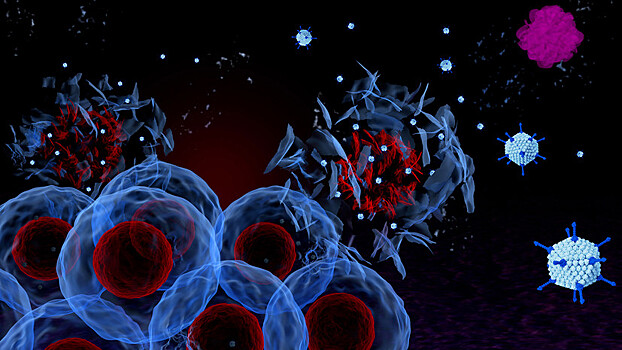

Российские учёные создали ряд модифицированных вирусов, которые вызывают гибель раковых клеток. Новая методика успешно испытывается на людях, которым не помогают другие методы лечения, заявляют исследователи. RT побеседовал с автором метода, членом-корреспондентом РАН, профессором и главным научным сотрудником Института молекулярной биологии РАН Петром Чумаковым. — Пётр Михайлович, могли бы вы рассказать, в чём заключается суть вашего метода? — Есть вирусы, которые могут подавлять рак. Они обладают онколитическими свойствами. И они безвредные для здоровья человека. Этот способ лечения практически не даёт побочных эффектов. Возможно только кратковременное повышение температуры, что является положительным признаком, говорящим о том, что вирус в организме прижился и оказывает реакцию. Это легко снимается обычными жаропонижающими средствами. — Когда метод станет широко применяться в практической медицине? — Сейчас основная наша задача — сертифицировать те препараты, которые у нас есть. Эта работа поддерживается Минздравом и Минобрнауки. У нас есть несколько грантов, по которым мы испытываем эти препараты. Мы делаем новые варианты онколитических вирусов с усиленными свойствами. Скоро должны начаться доклинические испытания в Институте имени Смородинцева в Санкт-Петербурге. Мы уже передали туда препараты. Врачи говорят, что на испытания уйдёт месяцев пять-шесть. Учитывая ситуацию с коронавирусом, я думаю, что в начале 21-го года испытания могут быть закончены, и тогда мы уже сможем договариваться с клиниками о проведении клинических испытаний. — Что собой представляет препарат, который должен пройти испытания? — Препарат — это живой вирус, который выращивается на культурах клеток. Это лекарство нового типа, которого не нужно много. Важно, чтобы он попал в организме в те клетки, которые чувствительны к нему. А дальше он сам размножается. То есть, лекарство само себя воспроизводит уже в том месте, где оно нужно. Это раствор, 100 миллионов вирусных частиц в одном миллилитре. Но самая большая проблема в этом лечении — это способ доставки вируса в опухоль, в случае с глиобластомой — в мозг, в ту область, где находится опухоль. Если препарат ввести просто внутривенно, то очень небольшая часть вируса может попасть в опухоль. В кровотоке есть неспецифические факторы, которые этот вирус быстро инактивируют. Кроме того, в мозгу есть гематоэнцефалический барьер, который препятствует попаданию туда всяких нежелательных агентов, в том числе и вирусов. Поэтому вирусу очень трудно добраться до опухоли. — Как вы смогли решить эту проблему? — Мы разработали другой способ доставки — с помощью иммунных клеток самого пациента. Для этого берётся кровь пациента, оттуда выделяются компоненты так называемой «белой крови» — лейкоциты. Они содержат очень много разных типов клеток. Чтобы выделить нужные для нас клетки, которые могут направленно идти в опухоль, мы проводим фракционирование этой «белой крови». И определенную фракцию, моноциты заставляем дифференцироваться в дендритные клетки. Потом эти дендритные клетки мы заражаем в пробирке онколитическим вирусом, и вводим внутривенно. Эти клетки, как торпеды, идут в очаги воспалений, где находится опухоль. Там вирус выходит из них и начинает убивать опухолевые клетки. Этот метод мы уже отработали на нескольких пациентах. Есть хорошие примеры, когда на МРТ или КТ видно, как опухоль уменьшается и исчезает. Но это происходит не у всех. — Почему же одни и те же вирусы не справляются с одними и теми же видами опухолей? — Дело в том, что каждый конкретный вирус нашей панели действует только на 15—20% пациентов. Остальные оказываются к вирусу устойчивы. Однако у нас есть много разных вирусов, и мы можем подобрать свой для любого пациента. Но для этого нужно иметь живые клетки пациента. Сейчас мы разрабатываем такие тесты, которые могут по обычной биопсии быстро показать, к какому вирусу опухоль будет чувствительна. Это очень сложная работа. Возможно, в будущем специальные клинические лаборатории будут получать от пациентов все необходимые материалы, и в режиме конвейера проводить тестирование, подбирать препараты, и далее — лечение. Но, сейчас к нам обращаются те, кому уже никто не может помочь. Некоторые из них лечатся у нас по полгода и более. Если идёт стабилизация, и видно, что опухоль не растёт, мы делаем перерыв до тех пор, пока рост не возобновится. Но есть случаи, когда рост не возобновляется. У нас есть пациент, который живёт уже четыре года, притом что шансов у него не было. Глиобластома — это смертельное заболевание, средняя продолжительность жизни с ним — 12–15 месяцев с момента постановки диагноза. — Пётр Михайлович, 14 мая на совещании о развитии генетических технологий в Российской Федерации директор института молекулярной биологии им. В.А. Энгельгардта Александр Макаров рассказал президенту о вашей методике лечения, и привёл в пример Анастасию Заворотнюк, которой была сделана подборка вирусов, способных победить её болезнь. После этого к нам обратилась героиня одного из предыдущих наших материалов Екатерина Калашникова. В обращении она написала, что представляет «группу пациентов в количестве 400 человек и их родственников». Она интересовалась, как попасть к вам на лечение. Есть ли у этих людей возможность получить такое лечение? — Прежде всего, должен сказать, что пока это экспериментальное лечение. Когда Макаров доложил об этой методе на совещании у президента, мне кажется, он не рассчитывал на то, что это вызовет такой резонанс. Сейчас меня буквально атакуют письмами десятки больных с просьбой помочь. Мне кажется, что не стоило рассказывать про Заворотнюк. Я знаю, что родные Анастасии долгое время вообще не комментировали её состояние, и не хотели, чтобы в прессе поднимали этот вопрос. Сам я Анастасию ни разу не видел. Ко мне обращались её близкие с просьбой о помощи. Я сказал, что мы могли бы на первом этапе протестировать её клетки. Дело в том, что во время операции были забраны живые клетки опухоли и переданы в один из институтов, где их удалось вывести в культуру клеток, чтобы они делились в пробирке. Мы взяли их и протестировали на чувствительность к нашим онколитическим вирусам, которые мы рассматриваем как средство лечения глиобластомы. Обнаружилось, что из 30 вирусов 7-8 вполне подходящие. И на этом этапе мы остановились, потому что муж Анастасии Пётр Чернышов сказал, что сейчас ситуация более-менее спокойная, если будет крайняя необходимость, они к нам обратятся. Это всё, что касается Заворотнюк. Но всё это мы делали и делаем в очень ограниченном масштабе. Сейчас, когда всё выплеснулось в СМИ, мы просто не справимся с таким валом пациентов. — Можете ли прокомментировать зависимость ЭКО и появления глиобластомы? Есть такие исследования? — Как я понимаю, этот вопрос опять поднят историей Заворотнюк. В данном случае, у неё было ЭКО. Но это никак не говорит о том, что есть какая-то связь. Во-первых, ЭКО не так много делают, и глиобластомы — это 1% всех опухолей. Глиобластома встречается не только у женщин. Я думаю, что никакой связи нет. Ведь как может воздействовать ЭКО? Повышается уровень половых гормонов. Но тех гормонов, которые, достаточно физиологичные и так всегда есть в организме. Они просто появляются в другое время и в другой дозе. И вряд ли могут оказать влияние именно на глиальные клетки, с тем, чтобы они переродились. — В мире ведутся подобные исследования по лечению глиобластомы? Что вам известно об этом? — Мы не первые, кто проверяет вирусы на глиобластоме. Сейчас это очень горячая тема во всём мире. И разные вирусы тестируют для лечения разной онкологии во многих странах. Я знаю один случай, который начали лечить в 96-м году вирусом «болезни Ньюкасла», это птичий вирус. И больной до сих пор живёт с глиобластомой. Это опубликованные данные. И есть ещё несколько случаев лечения с помощью рекомбинантных вирусов герпеса. В прошлом году вышла очень нашумевшая работа о том, что 20% больных глиобластомой могут быть вылечены вакциной рекомбинантного вируса полиомиелита. Но нейрохирурги люди консервативные. Они ни за что не согласятся, даже в порядке эксперимента, проводить такие опыты на людях. Потому что они очень сильно рискуют, если будет осложнение. Поэтому мы должны дожидаться доклинических испытаний с тем, чтобы потом убедить их опробовать схему с прямым введением вируса прямо в опухоль. — А кто и когда впервые заметил действие вируса на раковые клетки? — Еще в начале 20-го века учёные заметили, что опухолевые клетки особенно хорошо размножают вирусы. После инфекционных вирусных заболеваний у некоторых больных при разных видах рака наблюдались ремиссии. И уже тогда возникла мысль о том, что в будущем можно будет лечить онкобольных с помощью вирусов. В 50-е годы в Америке проводились эксперименты по лечению рака безнадёжных больных с помощью патогенных вирусов. Считалось, что это меньшее зло по сравнению с самим раком. И тогда были получены положительные результаты. Но поскольку многие больные умирали от инфекционных заболеваний, возник очень большой резонанс. Врачи, которые начали это делать, дискредитировали всю эту область на долгие годы. Были введены дополнительные этические правила. Само упоминание о том, что вирусом можно лечить рак, стало табу. В 90-е годы уже стало понятно, как устроены вирусы, их структура генома. Учёные научились вводить изменения в геном вирусов, чтобы сделать их безвредными. И тогда во всем мире начался бум разработки препаратов на основе вирусов для лечения рака. Но тут новая беда. Этому стали сопротивляться фармацевтические компании. Потому что это совершенно другой способ лечения, который подрывает базу их благосостояния. В начале 10-х годов нашего века многие небольшие компании разрабатывали препараты, которые потом проходили какие-то клинические испытания, были показаны какие-то многообещающие свойства. Но фармацевтические компании скупали эти разработки, и практически прекращали деятельность этих небольших стартапов. — Удалось ли кому-нибудь преодолеть фармацевтическое лобби и зарегистрировать препарат? — Сейчас в мире зарегистрировано три препарата онколитических вирусов. Один препарат разрешён к использованию в США для лечения злокачественных меланом. Ещё один рекомбинантный аденовирус в Китае, и один энтеровирус в Латвии. Но, в общем-то, каждый из этих препаратов находит пока очень ограниченное применение, из-за того что все они действуют только на часть пациентов. — Пётр Михайлович, а как давно Вы ведёте свои исследования? — Всю жизнь, ещё с 70-х годов. Мне выпало такое время, когда мы в начале практически ничего не знали о вирусах. И по мере того, как мы что-то узнавали, мы вносили какой-то вклад в эту науку, и сами учились. И я начинал как раз с вирусов. Потом переключился на проблему рака — фундаментальные механизмы деления клеток: как нормальная клетка превращается в рак. А потом снова вернулся в вирусологию. Должен сказать, что и мои родители были вирусологами, они занимались противополиомиелитной кампанией. Моя мать в 70-е годы изучала, как у детей образуются антитела к полиомиелитной вакцине, и она обнаружила, что у многих детей не образуются антитела. Оказалось, что в кишечнике у детей в этой время шла бессимптомная инфекция другого безвредного энтеровируса. И он вызывал неспецифическую защиту от вируса полиомиелита. Поэтому вакцинный полиовирус не мог индуцировать антитела у этих детей. Эти безвредные вирусы были выделены из кишечника здоровых детей. И на их основе были созданы живые энтеровирусные вакцины, которые испытывались для того чтобы предотвращать какие-то ещё неизвестные инфекции. И вот мы решили возобновить тот подход, который был предложен моей мамой, когда используется панель энтеровирусов. Оказалось, что те больные, которые не чувствительны к одному вирусу, могут быть чувствительны к другому. Возникла идея подбора вируса под пациента. Мы разработали целую панель собственных вирусов, которые могут также обладать усиленными свойствами. Мы продолжаем эту разработку. — Ваши вирусы могут побеждать рак. А есть вирусы, которые вызывают развитие опухоли? — Да. Например, рак шейки матки в 95% случаев вызывается вирусом папилломы. Сейчас уже есть даже вакцины против онкогенных папилломовирусов 16—18-го серотипа, которые применяются для девочек, чтобы не заболевали раком шейки матки. Но это самый большой пример. У большинства видов рака, сейчас можно полностью исключить вирусную природу. — Вы используете естественные вирусы или конструируете их? — У нас разные есть вирусы. Как я говорил, первая панель была выделена из кишечника здоровых детей. Это природные непатогенные вирусы, которые, кстати говоря, хорошо защищают детей от многих вирусных инфекций. Кроме того, мы делаем синтетические и рекомбинантные вирусы, когда мы вводим определенные изменения в их состав, которые усиливают их онколитические свойства. — На планете есть ещё места, где может быть очень много вирусов, о которых мы ещё и понятия не имеем. Например, те, что живут в океанских глубинах. Как вы считаете, если вдруг кто-то возьмется за изучение океана, именно с точки зрения вирусов, там могут найтись полезные для вас? — Да, и сейчас это тоже очень горячая тема. Когда разработали метод секвенирования геномов, ДНК, РНК, то возник соблазн: профильтровать сточные воды, океанические воды, из прудов, морей. Уже пробурили скважину в Антарктиде к древнему озеру, чтобы посмотреть, что там и выделить оттуда биологические компоненты и секвенировать их. И оказывается, что нас окружает огромное количество вирусов, которые абсолютно безвредны. И такое впечатление, что наше исходное представление о вирусах, как о чём-то вредном и вызывающем только болезни — неверно. Болезнетворный вирус — скорее исключение, чем правило.